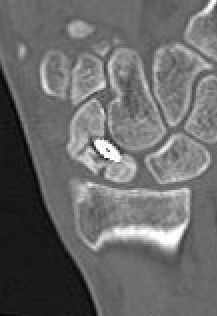

CT

Indication

- diagnose nonunion and identify size of cyst / defect

- identify humpback deformity

- helps to plan approach / size and shape of bone graft

Failure of fracture to unite at 3 months on CT scan

Nonunion with flexion / humpback deformity

Nonunion with flexion deformity